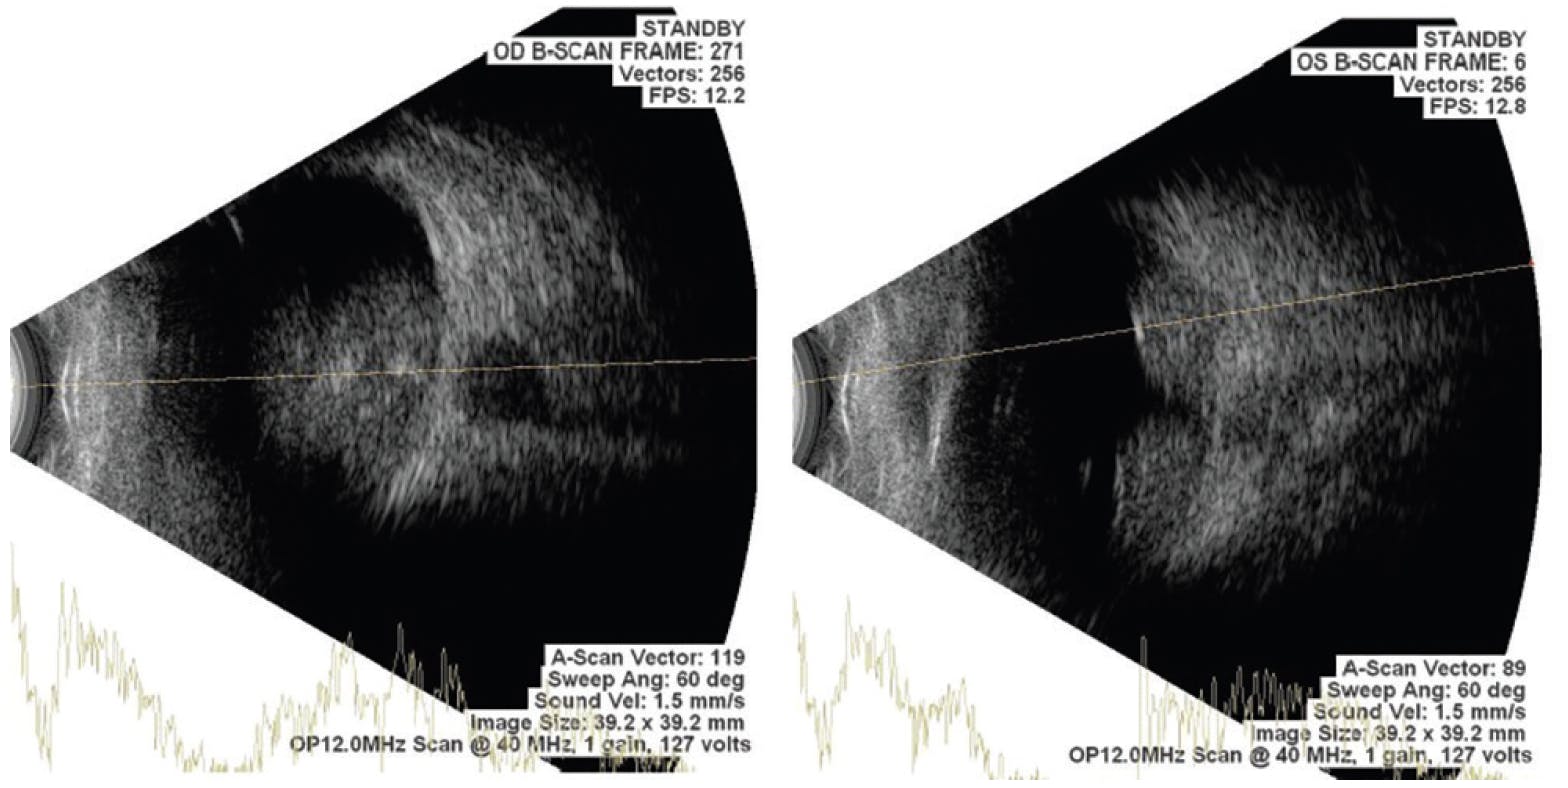

A 9-month-old boy presented with leukocoria in each eye since he was 2 months of age. Dilated fundus examination of each eye revealed multiple white lesions at the posterior pole with venous tortuosity and prominence involving the disc and macula, likely suggesting retinoblastoma. Ultrasound of each eye showed heterogenous mass-like lesions with moderate to high spikes suggestive of calcification associated with retinoblastoma (Figure 8). The patient was referred to an ocular oncologist.

<p>Figure 8. Ultrasound of each eye shows heterogenous mass-like lesions with moderate to high spikes, suggestive of calcification associated with retinoblastoma.</p>

Figure 8. Ultrasound of each eye shows heterogenous mass-like lesions with moderate to high spikes, suggestive of calcification associated with retinoblastoma.